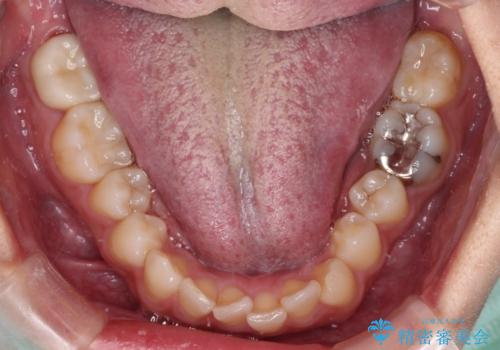

- 目立つ八重歯を気にして来院された患者様です。

上顎小臼歯を抜歯するかどうか悩みましたが、八重歯の後方に失活歯があること、治療前に上顎正中が概ね人中に合っていることから、右上第二小臼歯を抜歯することとしました。

片側での抜歯であると、正中が抜歯した方向にずれていくため、左上の奥歯を遠心移動させる目的でアンカースクリューと補助装置を併用した上で、ワイヤー装置にて矯正治療を行うこととしました。